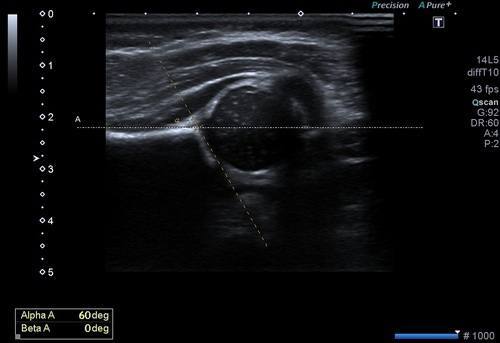

Bu inceleme de amaç her iki kalça eklemini oluşturan kemik yapıların, eklem ilişkilerinin ve kemik açılarının ölçülmesidir.

Bu ölçümler ile kalça gelişiminin normal olduğu, yavaş olup düzelme eğilimi olacağı ya da gelişim geriliği olduğu saptanır. Bu ölçümlerin optimizasyonu için uluslararası bir sınıflama sistemi kullanılır.